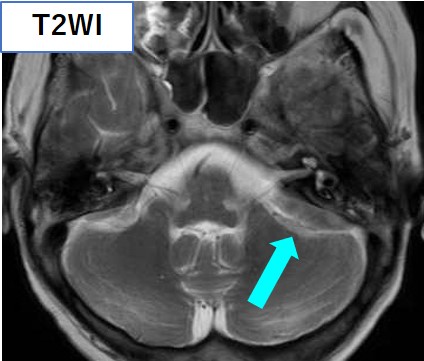

頭部CT・MRIにて、大脳鎌に沿った腫瘤を認め、左小脳橋角部にも腫瘤を認める。いずれもT1強調像で高信号、T2強調像で低信号を呈している。

頭部MRI

• 髄膜に沿った腫瘤形成(23%)

• 下垂体後葉のT1高信号が消失(47%)